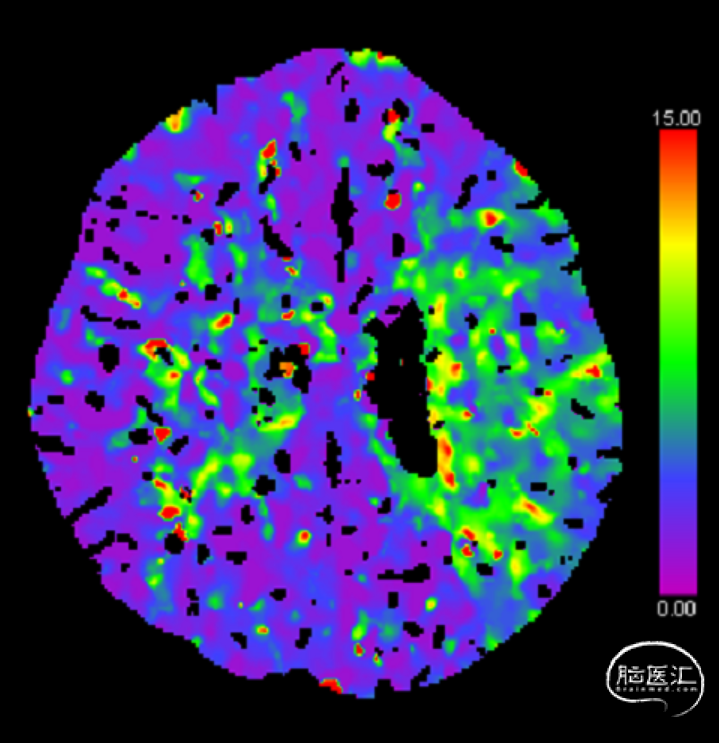

CTP:左侧大脑半球低灌注。

2、CTP 低灌注I期:代偿期

2、左侧大脑半球低灌注